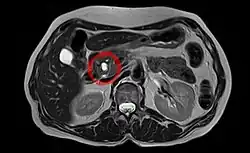

Neoplasia mucinosa papilar intraductal

Neoplasia mucinosa papilar intraductal é um tipo de tumor (neoplasia) que se desenvolve nos ductos do pâncreas (intraductal) e caracterizado pela produção de um líquido espesso pelas células do tumor (mucinosa).[1] Caso permaneçam por tratar, podem progredir para cancro invasivo maligno.